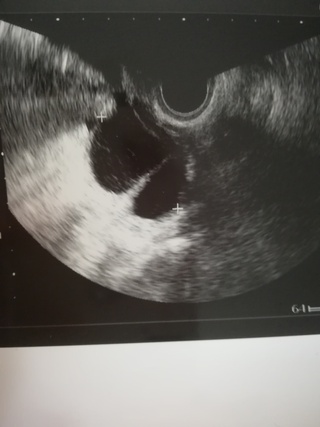

卵巣腫瘍 公益社団法人 日本産科婦人科学会

自覚症状がない 卵巣のう腫 は要注意 知っておきたい病気 医療 からだケアナビ

婦人科豆知識 卵巣腫瘍 さがらレディスクリニック

卵巣の病気 六本木ブレストレディースクリニック